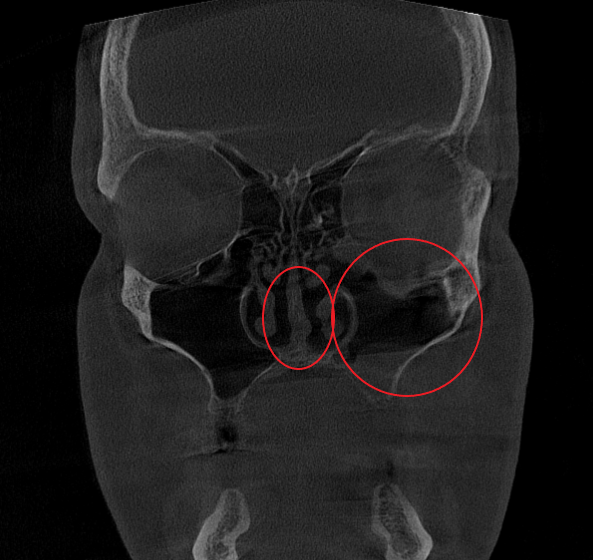

Послеоперационный период протекал гладко. Проводились регулярные туалеты полости носа, промывание оперированной пазухи, назначались средства для увлажнения и регенерации слизистой оболочки, а также местная антибактериальная терапия. По результатам оперативного лечения носовое дыхание было полностью восстановлено, признаки активного воспаления купированы. Спустя 1.5 месяца после проведенного оперативного лечения проведено КТ околоносовых пазух в динамике, что отражает промежуточный результат оперативного лечения. На снимках: Перегородка носа располагается по центру, оперативно созданное соустье левой верхнечелюстной пазухи функционирует, пневматизация левой верхнечелюстной пазухи значительно улучшилась. Окончательный результат можно будет оценить через 3 месяца после проведенной операции, и при полной пневматизации левой верхнечелюстной пазухи пациент сможет приступить к установке зубных имплантов в верхнюю челюсть слева.

- К установке имплантов пациент может приступить через 3 месяца после операции – при условии проведения контрольного КТ околоносовых пазух и полном восстановлении воздушности пазух.